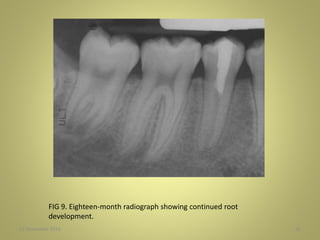

FIG 9. Eighteen-month radiograph showing continued root

development.

27 November 201656 FIG 9. Eighteen-month radiograph showing continued root development.